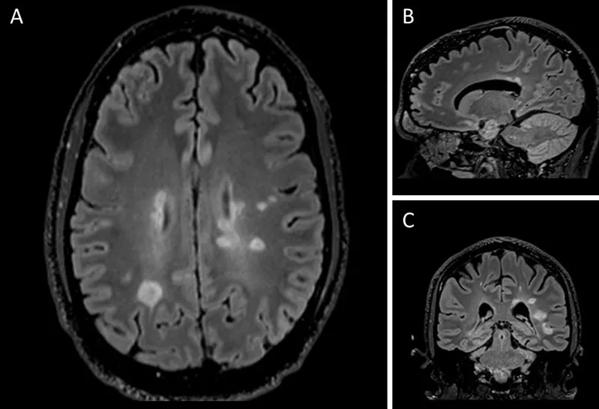

MRI images show central vein sign (CVS), a potential diagnostic biomarker for MS.

The CVS is an MRI-based biomarker identified in MS-associated white matter lesions. CVS criteria — scoring of a brain MRI based on the presence of the CVS — have been well validated as a sensitive and specific marker of MS in cross-sectional studies.